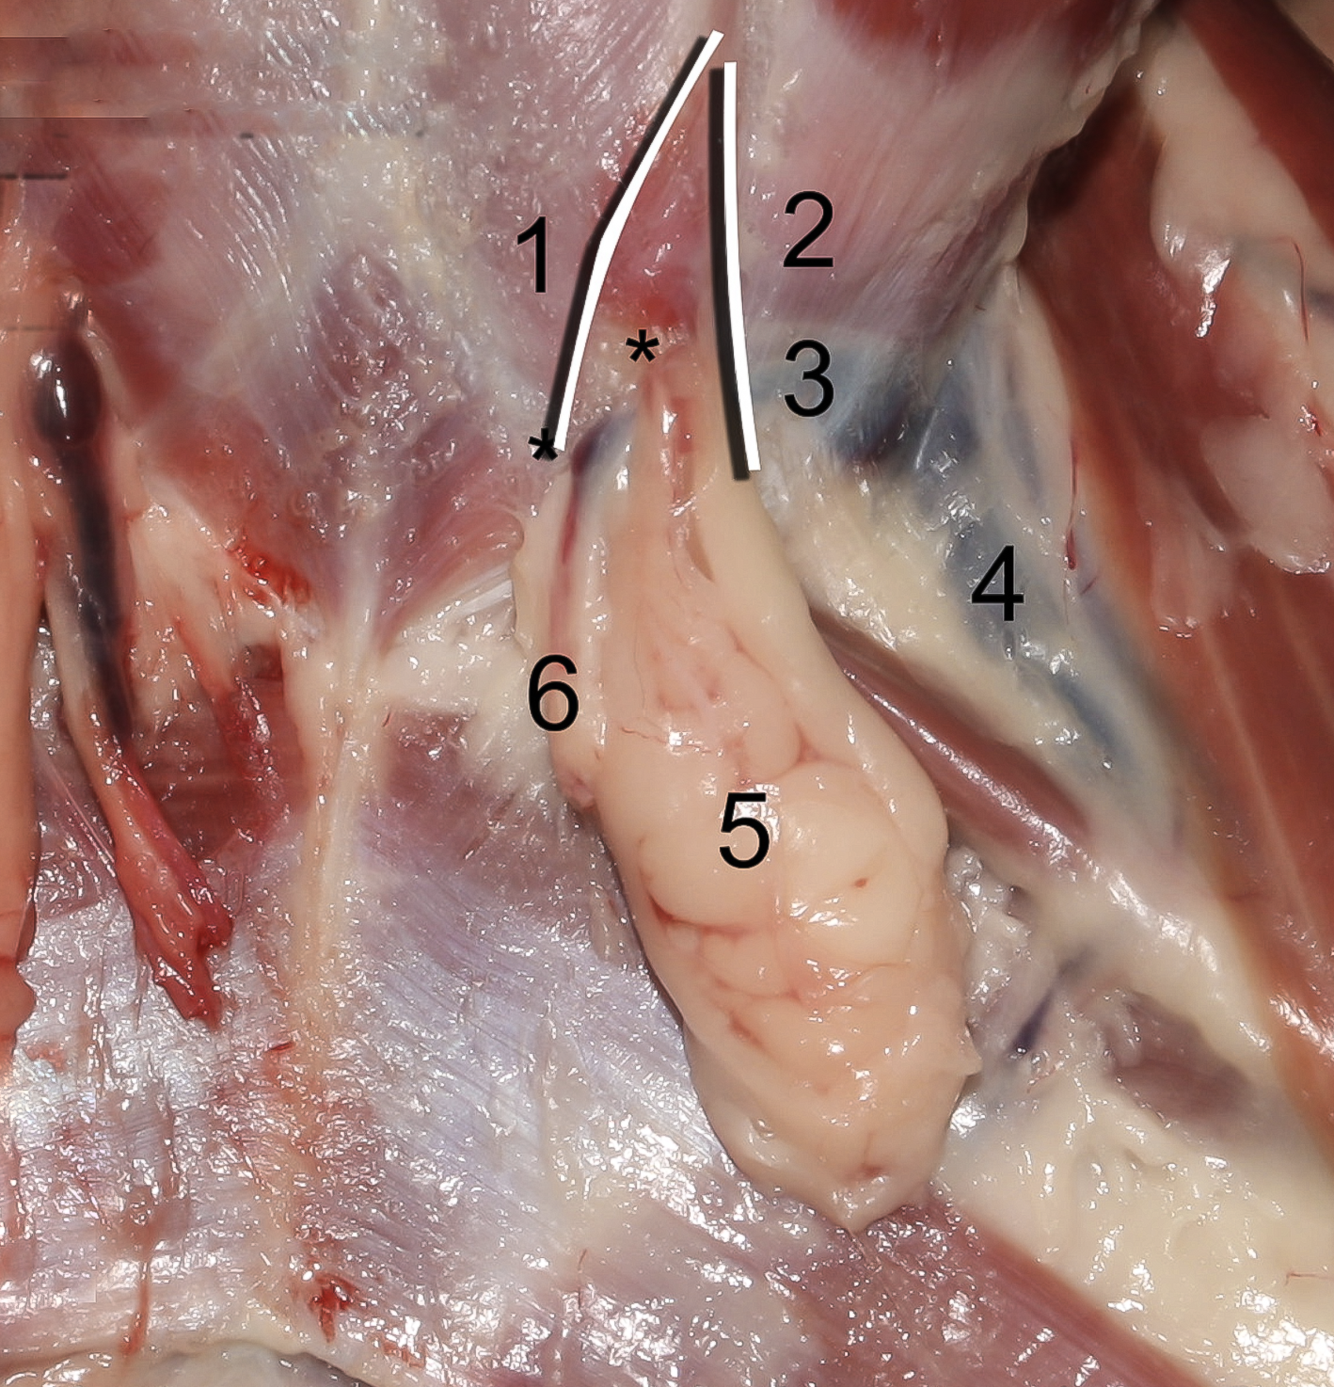

1

A

Crus mediale

6

Q

2

A

Crus laterale

7

Q

3

A

A./v. pudenda externa

8

Q

4

A

A./v. femoralis

9

Q

5

A

Processus vaginalis

10

Q

6

A

A./v. pudenda externa